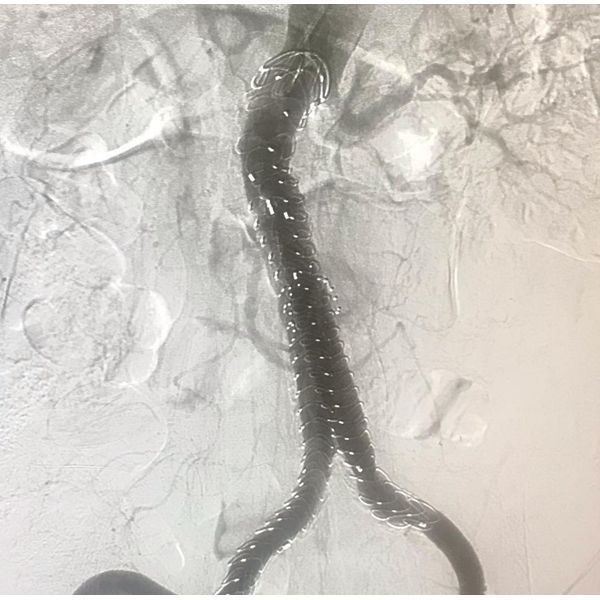

В плановом порядке ему установили стент-графт брюшной аорты.

Послеоперационный период протекал гладко, боль в пояснице исчезла. Через 4 дня после операции его выписали.

На контрольном осмотре спустя 10 суток новых жалоб не было. КТ-ангиография показала, что стент-графт плотно прилегает к стенкам аорты.